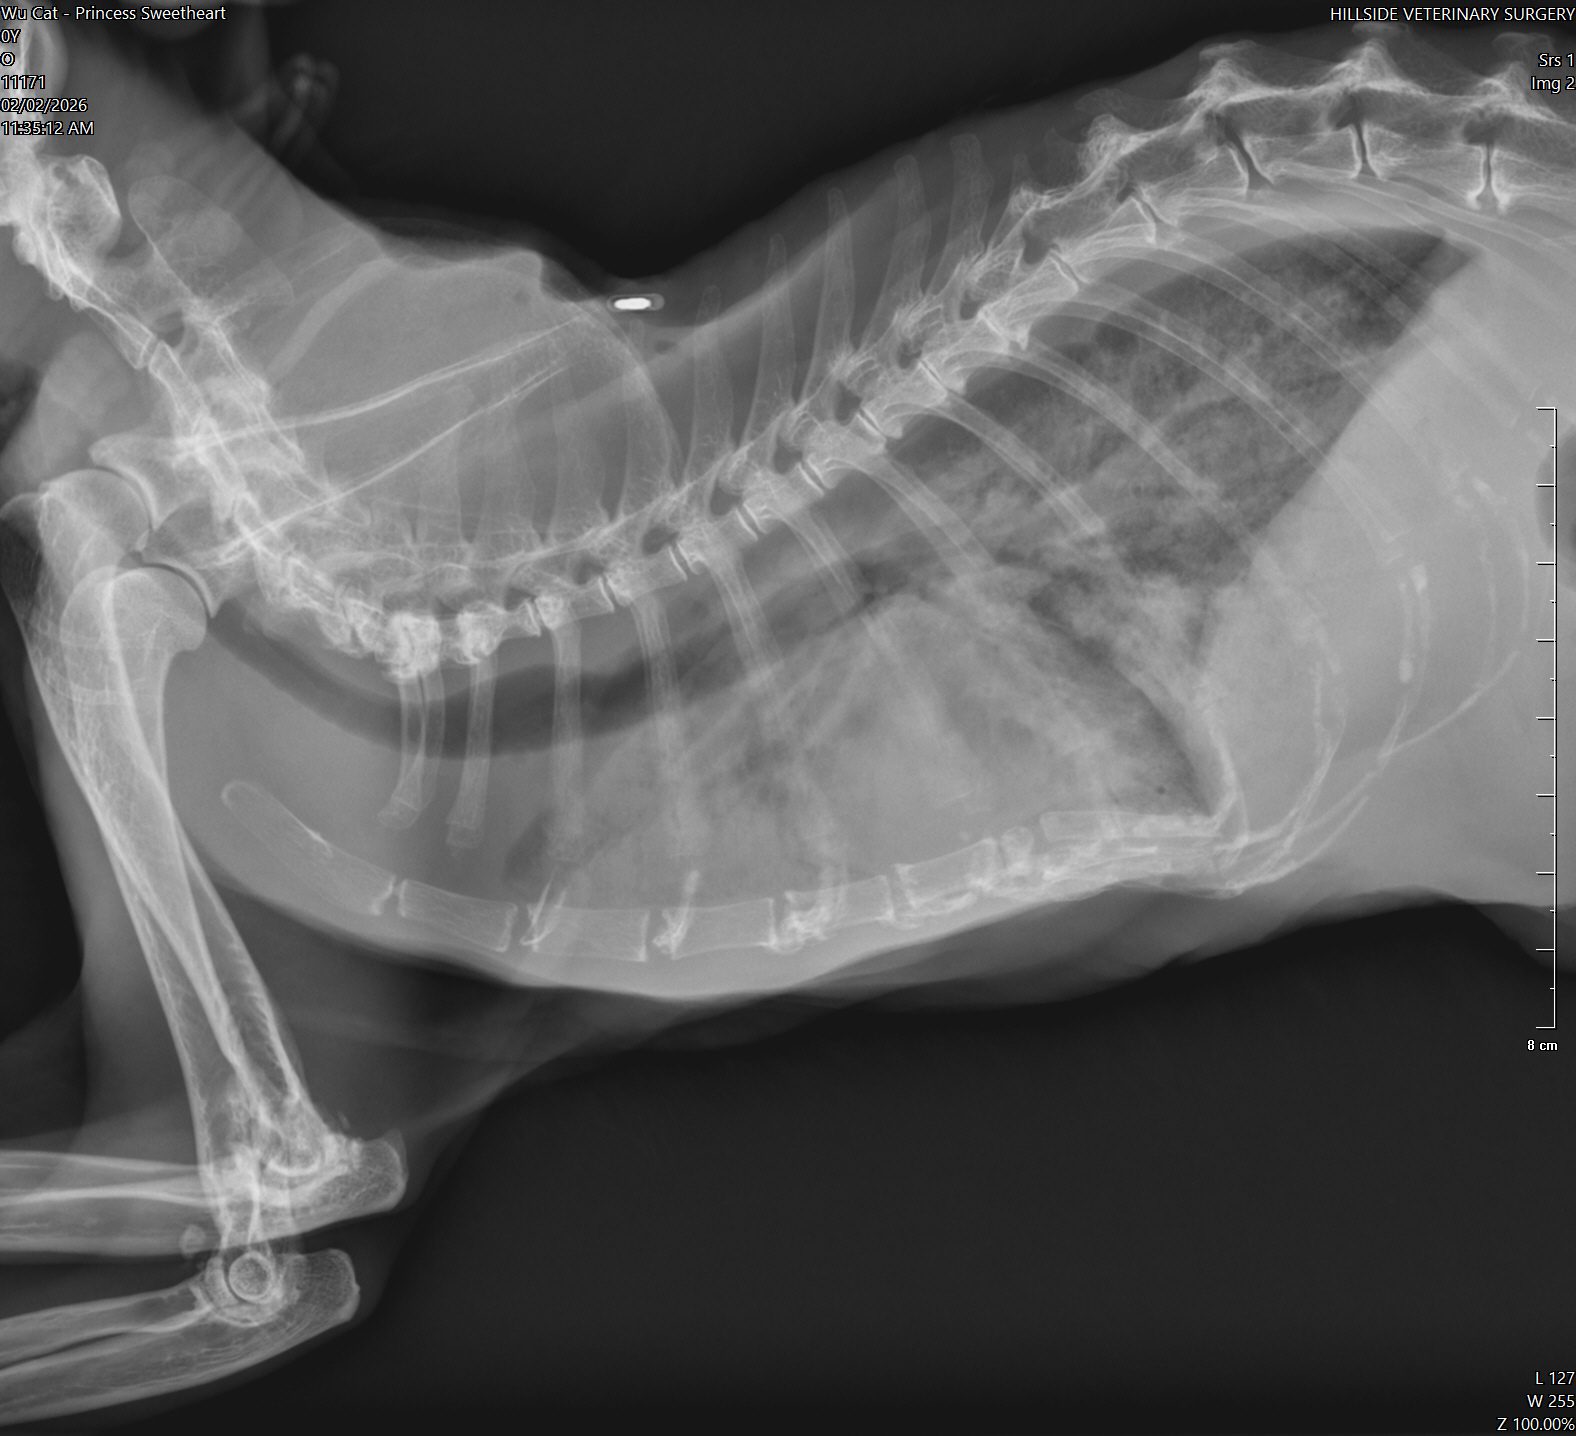

10am+: enter to bring boy for review, princess sianz look. Sleeping even though jo is serving food alr. Weird. I Subcut her as routine but i find her breathing labour. She is really weird. I feel that she might collapse. Jo serve tuna w gravy she is not keen, lucky when I serve tiny pouch she is keen but only take in 5%? Something very wrong she is 喘。 rush her to hillside w ah boy. Alison ard, she bring Ps in first to check, told her Ps is the heart/kidney combo. I taken her RR b4 she go in: 56.

11.15am: Dr Cheryl update: her o2 level low 80% only, she is going to take chest X-ray. most prob is fluid overload her heart le. She wanna retake her bloods, and most prob start frusemide which will stress the kidney but better than if the fluid can’t clear by kidney on time, her heart will fail and she die. That’s what I’m worrying about that why I bring her in cos I know heart scarier. She needs to stay in clinic in o2 for hours, cos to jab frusemide need to monitor in o2. Target 4.00-6.00pm.

Can hear from dr Cheryl tone: it’s serious. Later see the X-ray see how bad. I’ll definitely got to talk to princess let her relax in o2 n wait for me to fetch her when she feel better.

12.50pm; blood drawn, kidney aren’t as bad. Is her heart cannot take it. Lung full of fluid, can’t see her lung so she is a little drowning now, just hide very well. Frusemide given at 12.15pm, only can let frusemide do the job of draining fluid from lung. Can’t poke to draw cos not fluid ard lungs. Dr. Cheryl says Sure (high possibility) die by today. She is not flat yet, definitely panting, knew I’m here again. Sayang her n her head will tilt to me, move a little panting. I didn’t open her cage anything more than 20s. Let her max the use of o2.